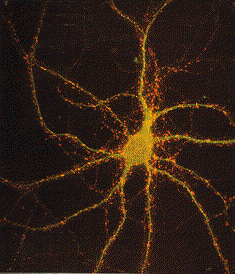

Neuron Dots Multiple Synopses

Brain Neuron - Dots are multiple synopses points